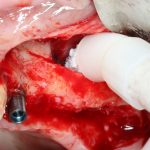

Я зафиксировал костный блок практически без адаптации на несколько винтов. Обрати внимание, что винты находятся в зоне, где не планируется установка имплантатов. Фиксация должна быть надежной, поскольку мне еще предстояла подготовка лунок для имплантатов. Трех винтов для этого вполне достаточно.

Дальнейшая адаптация костного блока свелась к сглаживанию острых краев. После чего я приступил к подготовке лунок и установке имплантатов.

Установка имплантатов.

Напомню, что для этой работы я выбрал субкрестальные имплантаты Ankylos C/X. Они прекрасно сочетаются с любым методом остеопластики.